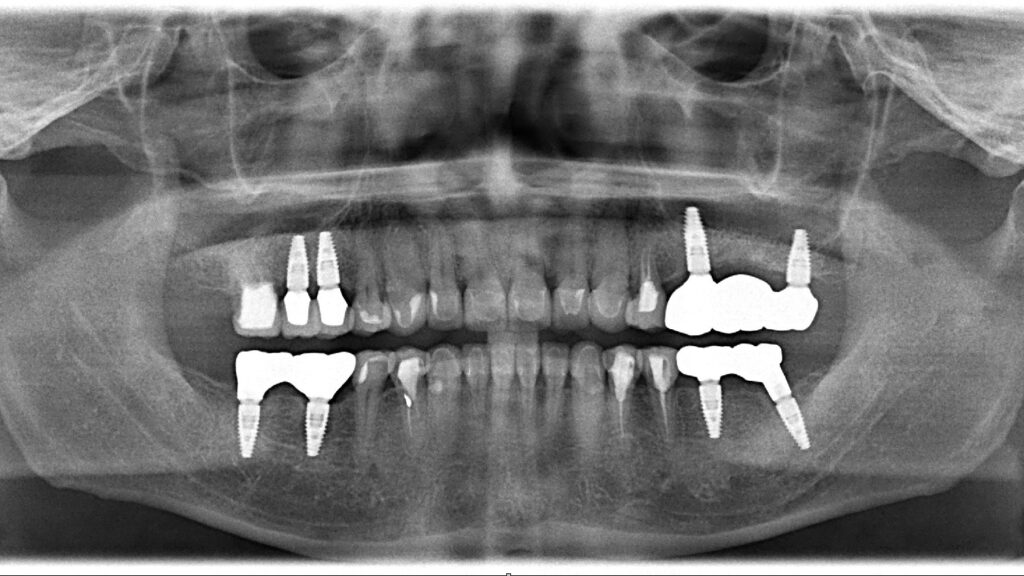

奥歯は傷みが酷く、確実にかみ合わせを支えるためにもインプラント治療となりました。後日インプラントオペの際は抜歯した歯牙に大量の膿が発生しておりました。

前歯は神経こそ有るもののCR(歯科用プラスチック)処置が多数施されており二次的な虫歯が発生しておりました。ここは健康な歯質のみを残し表面をセラミックで被せるオールセラミックス治療を行います。

| 治療方法 | インプラント治療・セラミックス治療 |

| 抜歯部位 | 14,25,27,37,46,47 |

| 治療期間 | 11ヶ月 |

| 治療費 | 50万円/1本 |

| リスク 副作用 | インプラントオペによる一時的な炎症・出血や顔面の内出血、治療終了後のメンテナンス不足による歯周病やインプラント周囲炎、歯ぎしりや過剰な噛み締めによるセラミックスの破折。 |